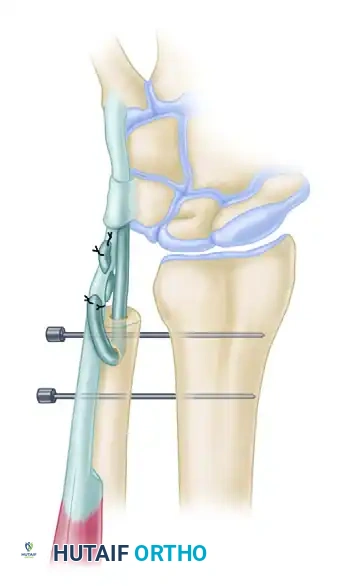

Step 3: Pronator Quadratus Mobilization and Transfer

- Identify the pronator quadratus muscle on the palmar aspect of the distal forearm.

- Dissect the pronator quadratus free from its palmar-medial attachment to the ulna. This requires meticulous elevation to preserve the muscle's integrity and its neurovascular pedicle (anterior interosseous nerve and artery), which enters the muscle on its deep, radial aspect.

- Mobilize the pronator quadratus radially. The muscle flap is then passed through the interosseous space or draped over the contoured ulnar stump.

- The transferred PQ acts as an interpositional arthroplasty, cushioning the space between the radius and ulna, while its new vector of pull actively retards dorsal translation ("winging") of the ulna during forearm rotation.

Figure 3: The pronator quadratus is mobilized and transferred to stabilize the distal ulnar stump, often secured with temporary K-wire fixation to maintain the radioulnar interval during healing.

Step 5: Temporary Osseous Stabilization

To protect the soft-tissue transfers while they heal, the radioulnar relationship must be rigidly maintained postoperatively.

- Position the forearm in neutral to slight supination (the position of maximum DRUJ stability).

- Manually reduce the ulnar stump to ensure an adequate radioulnar space (preventing convergence) and correct dorsal-palmar alignment.

- Drive two smooth 0.062-inch (1.6 mm) Kirschner wires (K-wires) transversely from the ulna into the radius. Ensure the wires engage both cortices of the radius for maximum stability.

- Cut the K-wires beneath the skin to prevent pin-tract infections, or leave them protruding through the skin with protective caps, depending on surgeon preference and patient reliability.